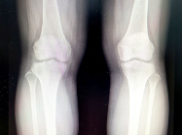

연골은 뼈를 흡수하고 완충시키는 뼈 사이의 부드러운 조직입니다. 연골은 피부와 마찬가지로 세포가 없고 외부 물리적 자극이 부족해 물질 교환이 제한적이다. 그 결과 연골손상은 자연치유가 어렵고 회복이 더디며 연골이 파괴되면 재생이 불가능할 수 있습니다. 연골 손상의 주요 원인은 부상, 나이, 비만, 스트레스 누적 등이다. 연골을 보호하기 위해서는 규칙적인 운동, 올바른 자세, 영양가 있는 식단, 스트레스 관리, 충분한 수면이 중요합니다.

연골 연화증은 연골 조직의 감소 및 퇴화를 특징으로 하는 질병입니다. 연골은 충격을 흡수하고 우리 몸의 움직임을 원활하게 해주는 뼈 사이의 연조직입니다. 연골 연화증은 연골 조직의 얇아짐과 부족으로 시작하여 결국 뼈와 뼈 사이의 마찰로 이어질 수 있습니다.

연골 연화증은 종종 관절염, 골관절염, 노화 또는 부상과 같은 원인에 의해 발생합니다. 비만, 고혈압, 당뇨병 및 유전적 요인과 같은 대사 질환도 연골 연화증의 발병에 기여할 수 있습니다. 연골연화증의 증상으로는 관절통, 감각이상, 운동장애, 관절변형 등이 있으며 특히 무릎, 고관절, 손목 등의 관절에 나타난다.